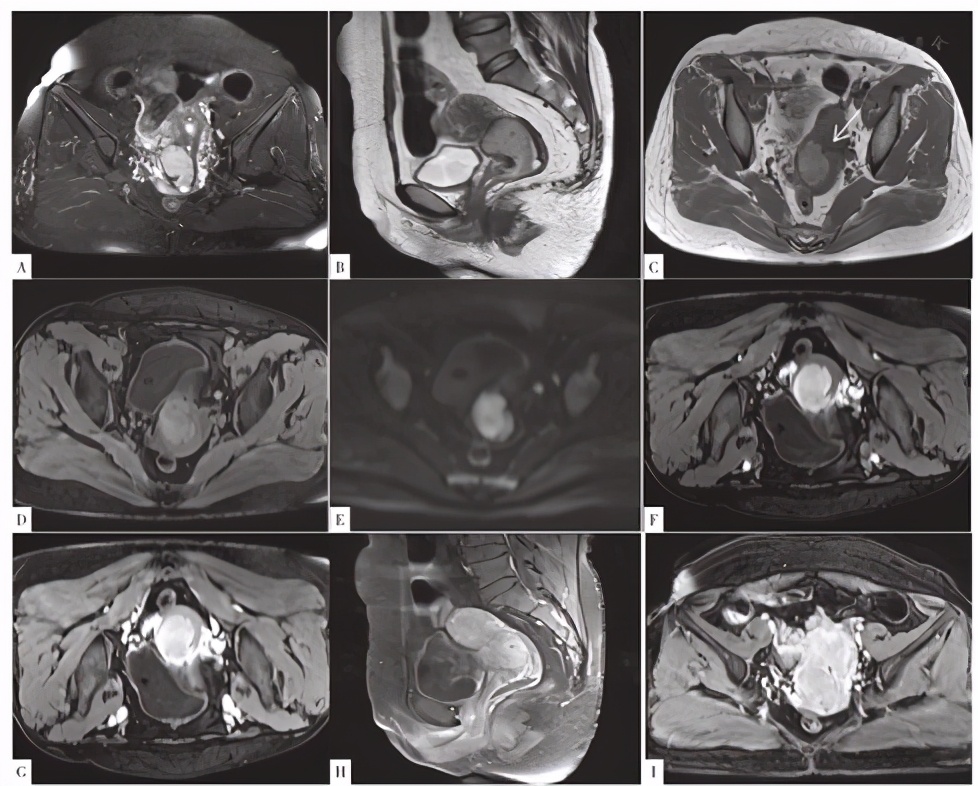

CT检查示:宫颈增粗,见一类圆形等密度占位,增强后动脉期明显均匀强化,静脉期呈等密度,边界尚清,大小31 mm×35 mm,盆腔左侧见数枚肿大淋巴结,见图1。MRI检查示:宫颈见一大小40 mm×35 mm×32 mm的占位,T1WI、T2WI以高信号为主,内见点状T1WI、T2WI低信号影,弥散受限,病灶边缘见流空血管,增强后病灶较均匀、明显强化,界尚清(见图2)。盆腔左侧见数枚肿大淋巴结。

图2 患者MRI检查结果

Figure 2 Result of uterus MRI

目前鲜见针对子宫PEComa的影像学报道,所见报道多认为子宫PEComa不具有特征性影像表现[2,3,4,9]。但本病例的影像表现具有一定的特征性。盆腔见数枚肿大淋巴结,提示子宫占位或为恶性肿瘤的可能。宫颈占位边界较清,明显较均匀强化,病灶边缘见粗大的血管,提示病灶血供丰富。肿瘤实性部分在MRI平扫图像上显现出特征性的T1WI、T2WI高信号表现,可能与肿瘤细胞内黑色素颗粒含量有关,本例患者病理检查图像可见一定数量的黑色素颗粒。研究发现,黑色素瘤可因黑色素含量不均匀而表现为混杂信号。ISIKLAR等[10]将颅内黑色素瘤根据黑色素含量不同分为4种类型:(1)黑色素型,T1WI呈高信号,T2WI呈低信号;(2)无黑色素型,T1WI呈低或等信号,T2WI呈高或等信号;(3)混合型,表现多变;(4)血肿型,只表现为出血的MRI特征。当黑色素瘤中黑色素细胞含量为10%时,才会出现黑色素顺磁性所致的典型黑色素瘤MRI特征,即T1WI呈高信号表现,T2WI呈低信号表现,具有高度特异性[10,11];无黑色素型、混合型及血肿型黑色素瘤均属于非典型性黑色素瘤,临床上罕见[12,13]。子宫PEComa与黑色素瘤一样含有黑色素颗粒,故笔者推测本例PEComa患者的MRI表现与肿瘤细胞内黑色素颗粒的含量密切相关。

本例子宫颈恶性PEComa患者应与下列疾病鉴别:(1)宫颈癌:表现为接触性出血,T1WI呈等低信号,T2WI较高信号,增强扫描后肿瘤于动脉期强化明显,门脉期及延迟期肿瘤呈轻度强化,与正常子宫肌层相比呈相对低信号,而本例子宫颈恶性PEComa患者无接触性出血表现,MRI表现亦不符合宫颈癌表现;(2)子宫颈癌肉瘤:子宫癌肉瘤瘤内异质性明显,常伴有坏死、囊变及出血,使得肿瘤信号混杂、强化不均,与本例患者较均匀强化的子宫颈恶性PEComa不同;(3)子宫颈肉瘤:T1WI呈等低信号,T2WI呈较高信号,分叶状,信号不均,常可见中心大片坏死区,增强扫描不均匀强化,边界不清,以囊性为主的病灶,其内小囊数目多且呈网格状改变,可作为子宫肉瘤的一种特征性表现,易可与本例子宫颈恶性PEComa鉴别;(4)子宫颈肌瘤伴变性:红色变性、脂肪、黏液变性表现为T1WI、T2WI高信号,但信号不均匀,脂肪变性区呈低信号,黏液变性区域增强无强化,且不伴有盆腔淋巴结肿大,可与子宫颈恶性PEComa鉴别。综上,以下影像表现结合病史可提示存在子宫PEComa的可能:(1)T1WI高信号;(2)宫颈肿瘤密度/信号相对均匀,强化均匀;(3)增强扫描中心或边缘见粗大迂曲强化血管。然而针对无特征性影像表现的子宫PEComa,仅能依靠病理诊断,免疫组化尤其重要[14]。